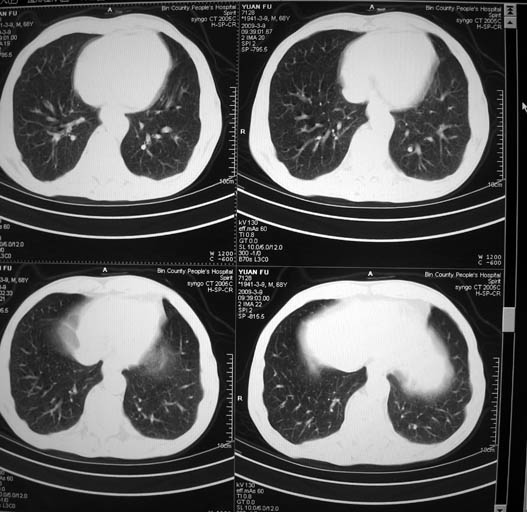

标题: CT18577:男,68岁,左肺占位。 [打印本页]

标题: CT18577:男,68岁,左肺占位。

男,68岁,左上肺占位,肺门淋巴结转移?

1)考虑左肺上叶尖段周围型肺癌并阻塞性肺炎,纵隔淋巴结转移。2)心包少量积液。

1)考虑左肺上叶尖段周围型肺癌并阻塞性肺炎,纵隔淋巴结转移。2)心包少量积液

1)考虑左肺上叶尖段周围型肺癌并阻塞性肺炎,纵隔淋巴结转移。

2)心包少量积液。